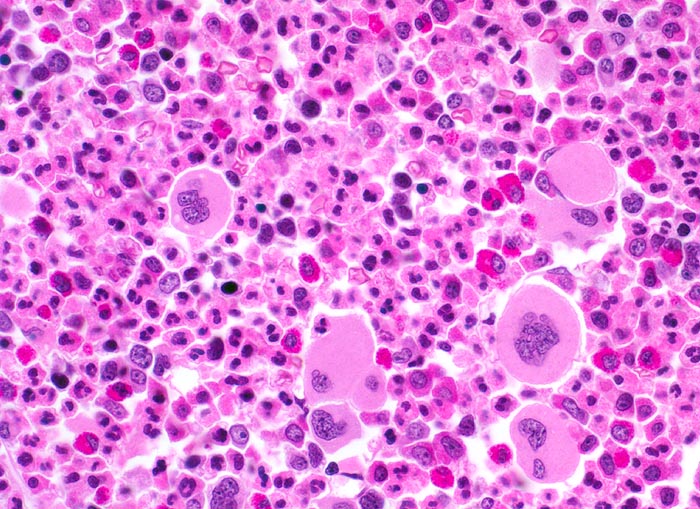

In der chronischen Phase zeigt das Knochenmark eine Hyperzellularität, welche auf eine Vermehrung der neutrophilen Granulozyten und deren Vorläufer zurückzuführen ist. Der paratrabekuläre Streifen unreifer Granulozyten kann verbreitert sein von normal 2-3 Zellschichten auf 5-10 Zellschichten. Blasten machen weniger als 5% der Knochenmarkzellen aus. Eine Blastenzahl von mehr als 10% deutet auf eine Transformation in ein akzeleriertes Stadium und von mehr als 20% entspricht einer Blastenkrise mit Transformation in eine akute Leukämie. Die Megakaryozyten sind typischerweise kleiner als normal, haben hypolobierte Kerne und sind bei 40-50% der Patienten vermehrt. Der Prozentanteil der erythroiden Vorstufen ist gewöhnlich vermindert (G:E Ratio >5:1. Die initiale Knochenmarkbiopsie zeigt bei 40% der Patienten eine Vermehrung von Reticulinfasern assoziiert mit einer erhöhten Anzahl Megakaryozyten. Das Ziel der histologischen Untersuchung des Knochenmarks besteht darin, den Anteil an Blasten im Knochenmark und damit das Stadium der Erkrankung festzulegen. Bis zu einem Blastengehalt von weniger als 10% der kernhaltigen Zellen spricht man von einer chronischen Phase, zwischen 10 und 20% von einer akzelerierten Phase und bei über 20% liegt eine akute Leukämie vor.

• Der paratrabekuläre Saum unreifer myeloischer Zellen ist verdickt auf 5 bis 6 Zellen.

• Verdrängung der Erythropoese.

• In Gruppen liegende vermehrte nacktkernige (= kein Zytoplasma) verkleinerte Mikromegakaryozyten mit hypolobierten Kernen.